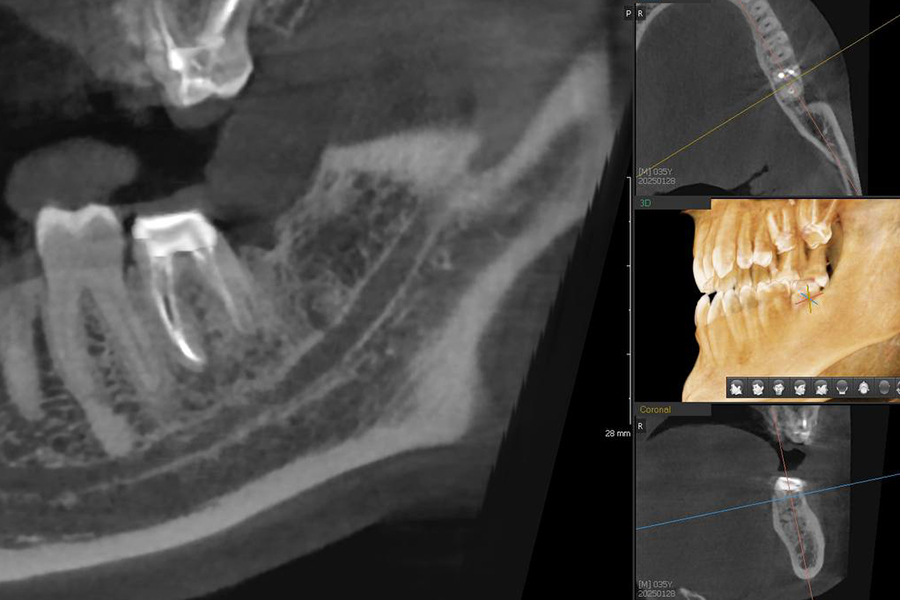

Результат

По результатам КЛКТ мы наблюдаем положительную динамику, уменьшение очага деструкции костной ткани